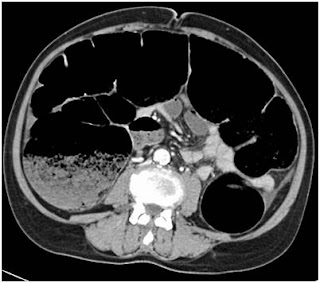

An elderly woman in her 8th decade presented with 6 months history of weight loss and progressive constipation that for last 4 days had progressed to obstipation. There was no major comorbid illness and prior to obstipation she was managing her daily activities. Her abdominal CT scan revealed obstructing lesion in rectosigmoid region with closed loop obstruction. There were multiple colorectal liver metastases in segment 2 & 3 (Figure 2 & 3).

Figure 3. Abdominal CT scan showing closed obstruction of large bowel

At surgery, the whole of whole of large bowel was massively distended but the cecum was viable. Anterior resection with ascending colostomy was done. She opted for colostomy closure 8 weeks later but declined further chemotherapy. Following this second surgery she was restored to good quality of life and passed away 16 months later.